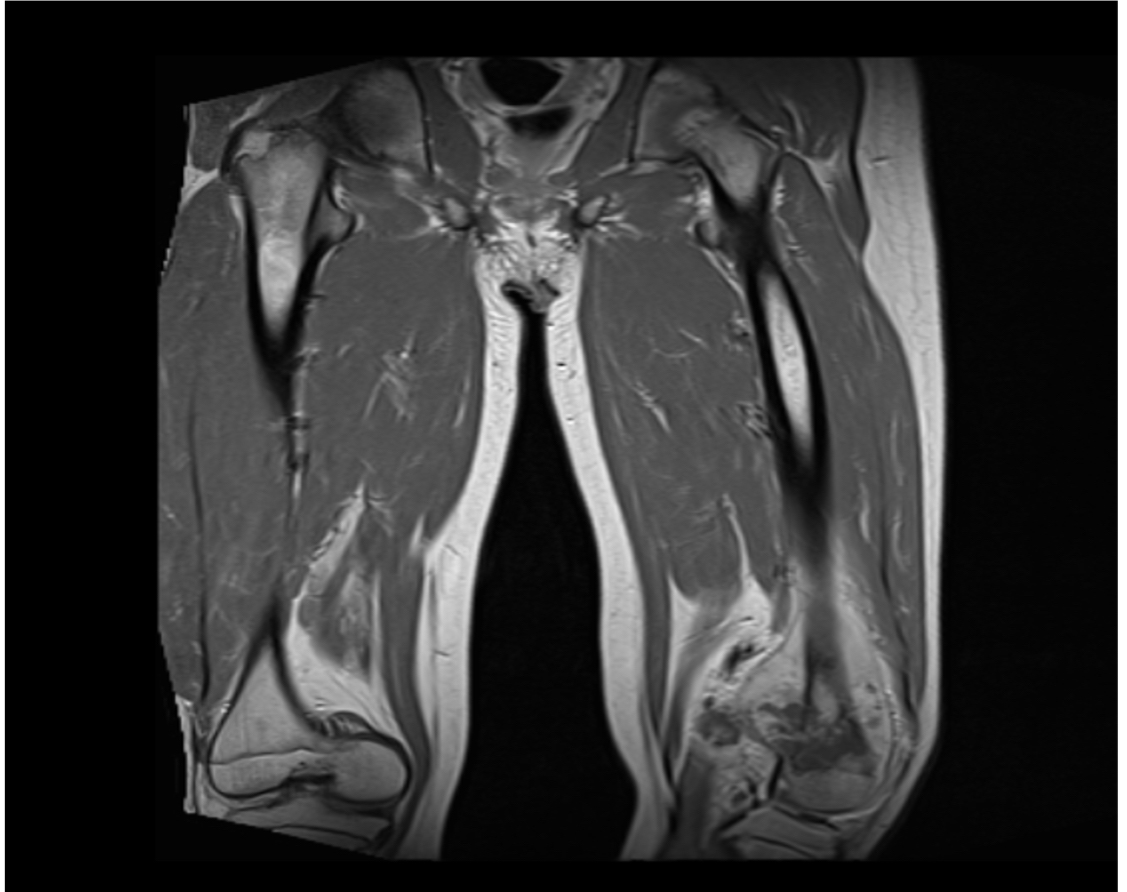

Figura 2. RNM de MIII con contraste.

Lesión de aspecto tumoral a nivel distal del fémur, con compromiso del núcleo de crecimiento medial e hidroartrosis. Figura 3.

Figura 4. RNM de fémur comparativa

Lesión tumoral hiperintensa con calcificación a nivel periostal del fémur de origen infiltrativo y con aumento de partes blandas por proceso neoplásico, compromete el núcleo de crecimiento medial del fémur a nivel periostótico con captación diseminada del material de contraste. Cambio osteopénicos y edema de y tejidos blandos.